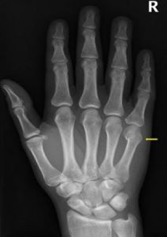

Bij een gebroken 5e middenhandsbeentje heeft u een breuk in de buurt van de knokkel van uw pink. Bij eenvoudige breuken krijgt u voor de behandeling meestal tape en een drukverband. Bij complexere breuken, waarbij er bijvoorbeeld sprake is van een rotatie (draaiing) van de pink, wordt er soms gekozen voor gips en eventueel een operatie. In die gevallen is deze tekst niet van toepassing.